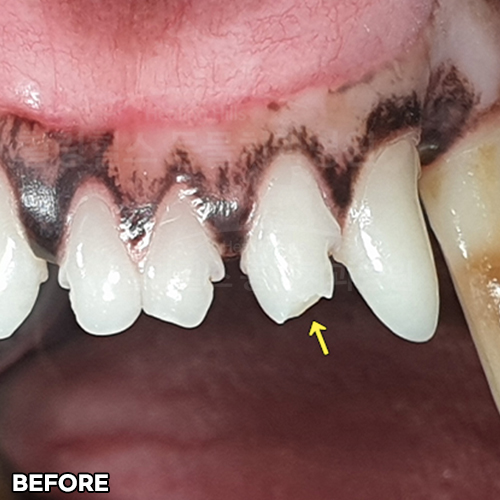

[깨진 강아지 치아 레진치료 전후]